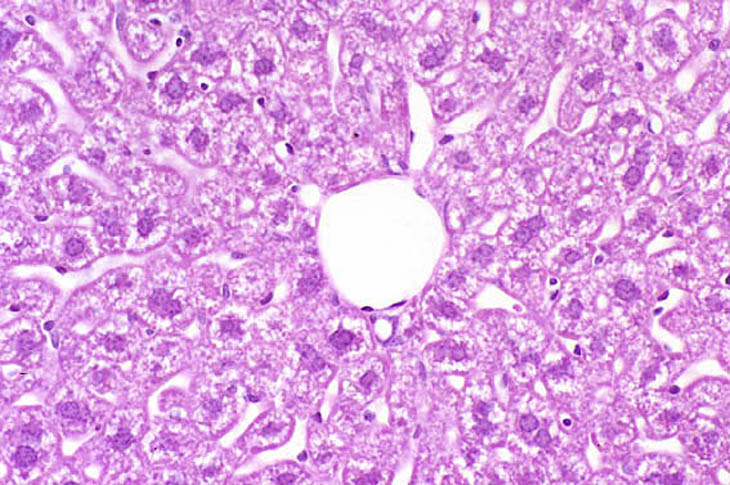

Perfusion fixation of the liver from a non-fasted mouse. Fixative was 10% NBF.